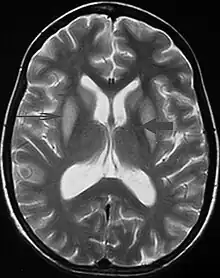

| Axial fat-saturated T2-weighted image showing hyperintensity in the pons with sparing of the peripheral fibers, the patient was an alcoholic admitted with a serum Na of 101 treated with hypertonic saline, he was left with quadriparesis, dysarthria, and altered mental status | |

It can be diagnosed clinically in the appropriate context, but may be difficult to confirm radiologically using conventional imaging techniques. Changes are more prominent on MRI than on CT, but often take days or weeks after acute symptom onset to develop. Imaging by MRI typically demonstrates areas of hyperintensity on T2-weighted images.[29]